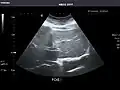

Abdominal Ultrasound (Full Exam)

STRUCTURED REPORT

(Technique: Transabdominal ultrasonography; Device: Toshiba Aplio XG)

Liver: Diffusely homogeneous and normal in echogenicity. No focal mass or contour nodularity. No intrahepatic biliary ductal dilatation.

Portal Vein: Patent main portal vein.

Gallbladder: No stones, wall thickening, or pericholecystic fluid.

Common Bile Duct: Nondilated measuring 1.3 mm at the level of the porta hepatis.

Pancreas: Visualized portions unremarkable.

Spleen: Normal in size.

Kidneys: Right and left kidneys measure 11.5 cm and 12 cm in length respectively. No hydronephrosis. Small left lower pole kidney cyst.

Ascites: None.

Aorta: Visualized portions normal in caliber, 16 x 15 mm.

IVC: Normal.

IMPRESSION:

Normal abdominal ultrasound.